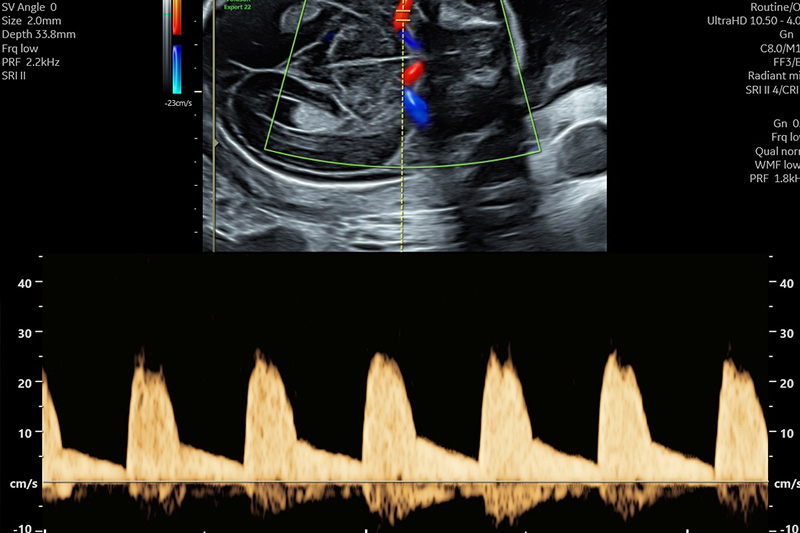

Doppler-sonografie

Die Dopplersonografie ist eine Untersuchung in der die Gefäße des Kindes, der Placenta und der Gebärmutter beurteilt werden. Insbesondere der Strömungswiderstand und die Blutflussgeschwindigkeiten

geben Aufschluss über eventuelle Risikokonstellationen und können in Fällen von kindlicher Wachstumshemmung den optimalen Geburtszeitpunkt für das Kind bestimmen.

Es ist möglich mittels Screening eine kindliche Wachstumshemmung und die Entwicklung einer Präeklampsie („Schwangerschaftsvergiftung“) abzuschätzen und die weitere Schwangerschaftsbetreuung individueller anzupassen.